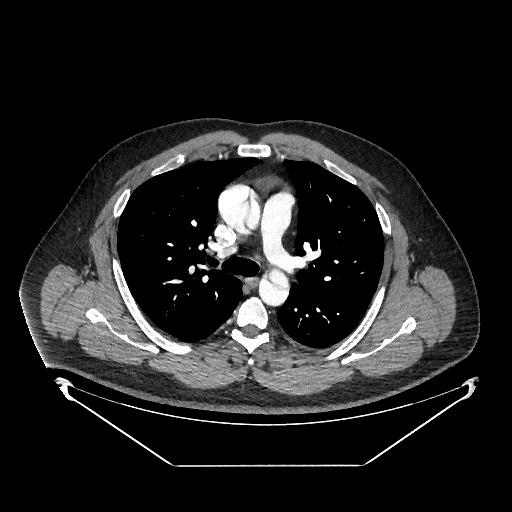

Um homem idoso apresenta-se em serviço de emergência com relato de dor torácica retroesternal de forte intensidade (10 de 10 em escala numérica) há cerca de uma hora, em rasgante, com irradiação para o dorso. Previamente hipertenso, com uso irregular de medicações, ao exame físico da admissão, estava lúcido e orientado, com fácies de dor, sudoreico, com pressão arterial de MSD 168 x 96 mmHg e MSE 130 x 50 mmHg, frequência cardíaca de 124 bpm, frequência respiratória de 20 rpm, temperatura de 36,7 ⁰C e saturação de 98%. Foram realizadas medidas de estabilização e exames complementares (mostrados a seguir).

Com base nesse caso hipotético, assinale a alternativa que apresenta a conduta a ser adotada após os resultados dos últimos exames realizados.